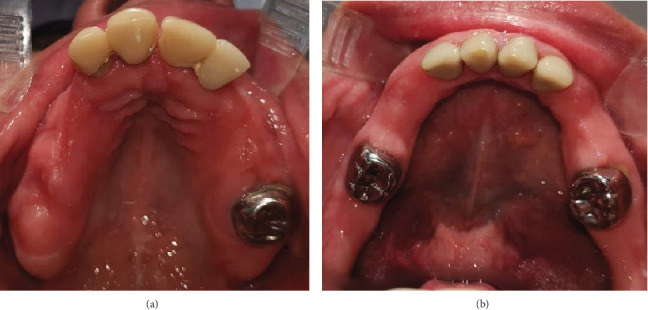

牙发育不良是一种影响牙齿成熟和形成的牙齿异常,导致牙釉质和牙本质发育不全和低钙化。它可以影响一个或几个象限的牙列,虽然广泛的累及是极其罕见的。确切的原因尚不清楚,但创伤、感染、营养或代谢不足被认为是可能的因素。诊断需要结合临床和放射学检查结果。临床上表现为小牙呈黄色或褐色变色,可影响初级和恒牙。放射照相时,放射密度降低,引起模糊或“鬼牙”外观。组织学上,这些牙齿表现为柱状牙釉质,球间牙釉质,以及被称为类牙釉质聚集体的牙釉质样钙化。治疗取决于牙齿受累的程度和患者的年龄。本文报告了一名31岁的女性,她在其普遍形式中表现出这种罕见的异常,使她成为文献中报道的年龄最大的患者。

Odontodysplasia is a dental anomaly that affects the maturation and formation of teeth, resulting in hypoplasia and hypocalcification of both enamel and dentin. It can affect one or several quadrants of the dentition, although generalized involvement is extremely rare. The exact cause is unclear, but trauma, infection, and nutritional or metabolic deficiencies have been suggested as possible contributing factors. Diagnosis requires a combination of clinical and radiological findings. Clinically, it presents as small teeth with yellow or brown discoloration, and it can affect both the primary and permanent dentition. Radiographically, there is reduced radiodensity, giving rise to a blurred or "ghost tooth" appearance. Histologically, these teeth show aprismatic enamel, interglobular dentin, and the presence of enamel-like calcifications known as enameloid conglomerates. Treatment depends on the extent of tooth involvement and the patient's age. This paper reports the case of a 31-year-old woman who presented with this rare anomaly in its generalized form, making her the oldest patient with this diagnosis reported in the literature.